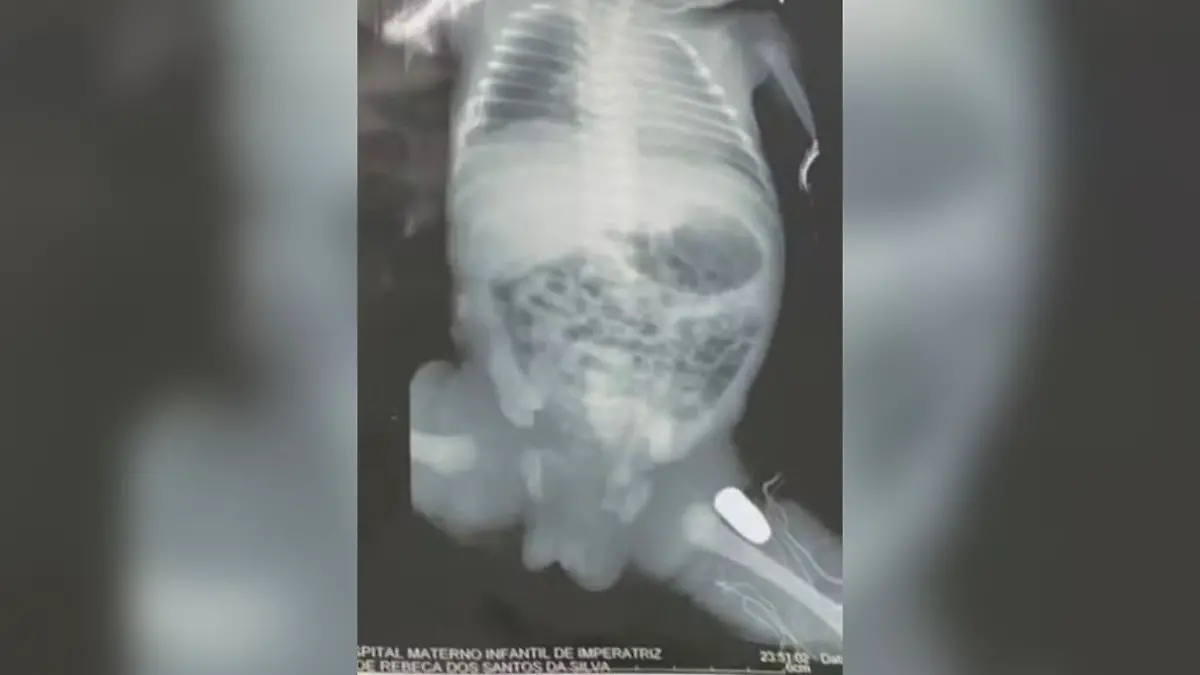

Die Männer hatten der Schwangeren mitten in den Bauch geschossen, wie das Nachrichtenportal g1 berichtet. Die 15-Jährige kam sofort ins Krankenhaus. Röntgenbilder zeigten, dass die Kugeln das linke Bein des 32 Wochen alten Babys getroffen hatten.